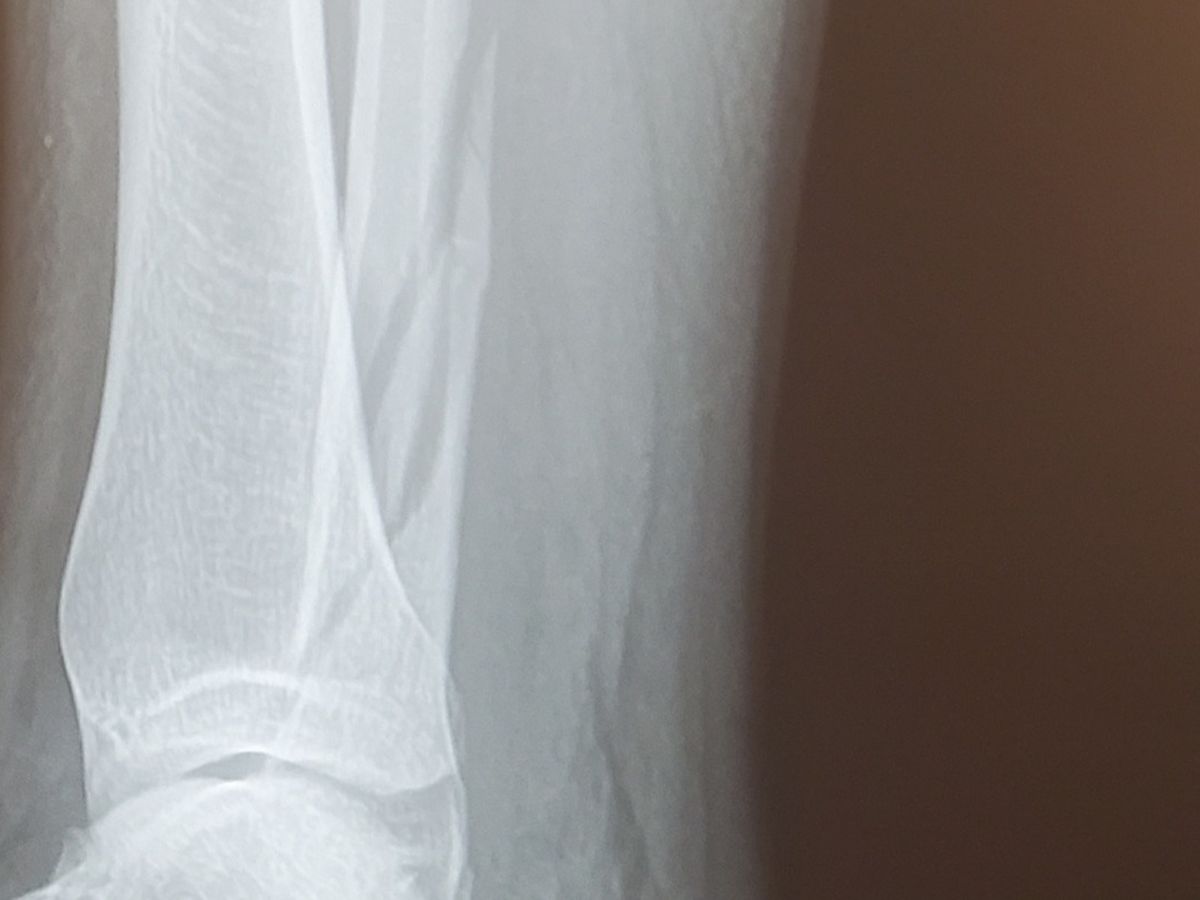

My insurmountable hospital bills just got worse. I broke my leg earlier this year and got bills that totaled about $5,000 more than I was expecting. I am currently without health insurance, as it is not offered through my work, so everything is coming out of pocket. I wasn't able to pay the original amount, and am struggling to figure out how to pay the now even larger amount having no more savings, no family to get money from, and having not been able to work for 5 weeks..

All of this will go towards paying for my hospital bills for my stupid leg deciding not to work, anything over will help recoup what I have already paid, and anything beyond that I will try to make sure I donate back to the community.